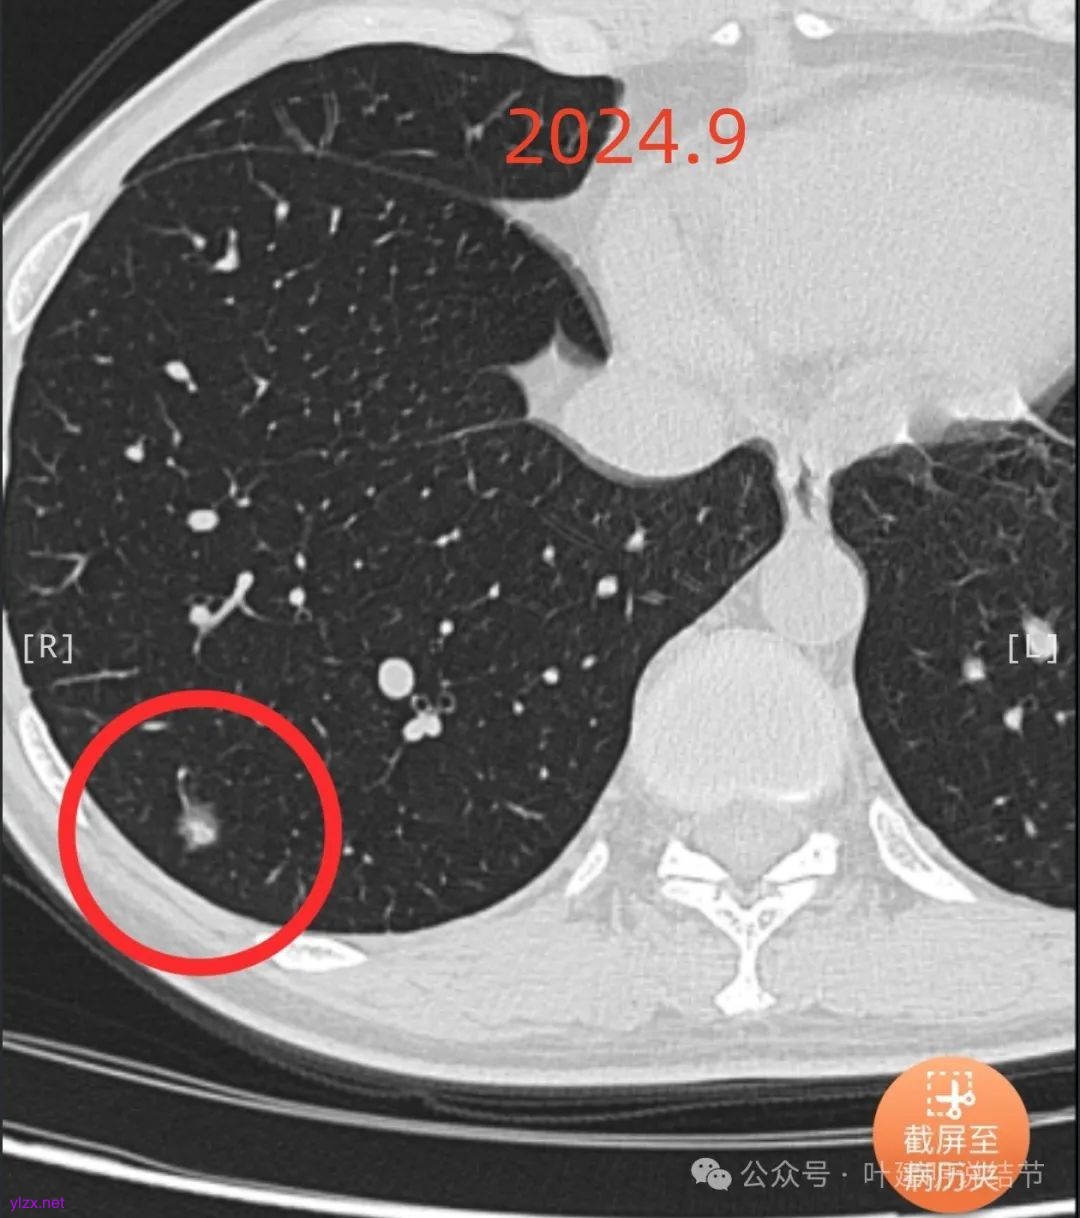

患者7年前在当地医院就诊时完善胸部CT发现肺结节,发现后未服用药物治疗,定期复查随诊,2024-09-29复查胸部CT提示:右肺下叶(薄234)见混杂密度小结节影,边缘毛糙,大小约0.8x0.7cm,其内见小血管穿行。双肺可见多发微小结节影,双肺见索条影,右肺可见小钙化灶。近期患者无咳嗽、咳痰、咯血、胸闷、胸痛、心慌、气急、头晕、头痛、畏寒、发热等不适,精神、饮食、睡眠正常,大小便正常,体重无明显变化。

2024年9月时病灶较前有所增大,实性成分增大,表面不平,棘突明显,进入血管有异常增粗。

逐层看了2024年的影像:

我又建议其还是切了好。但嘱咐她不管病理是什么类型,只做楔形切除,因为毕竟7年才长这么点,浸润性癌也不会是恶性高会转移的亚型。